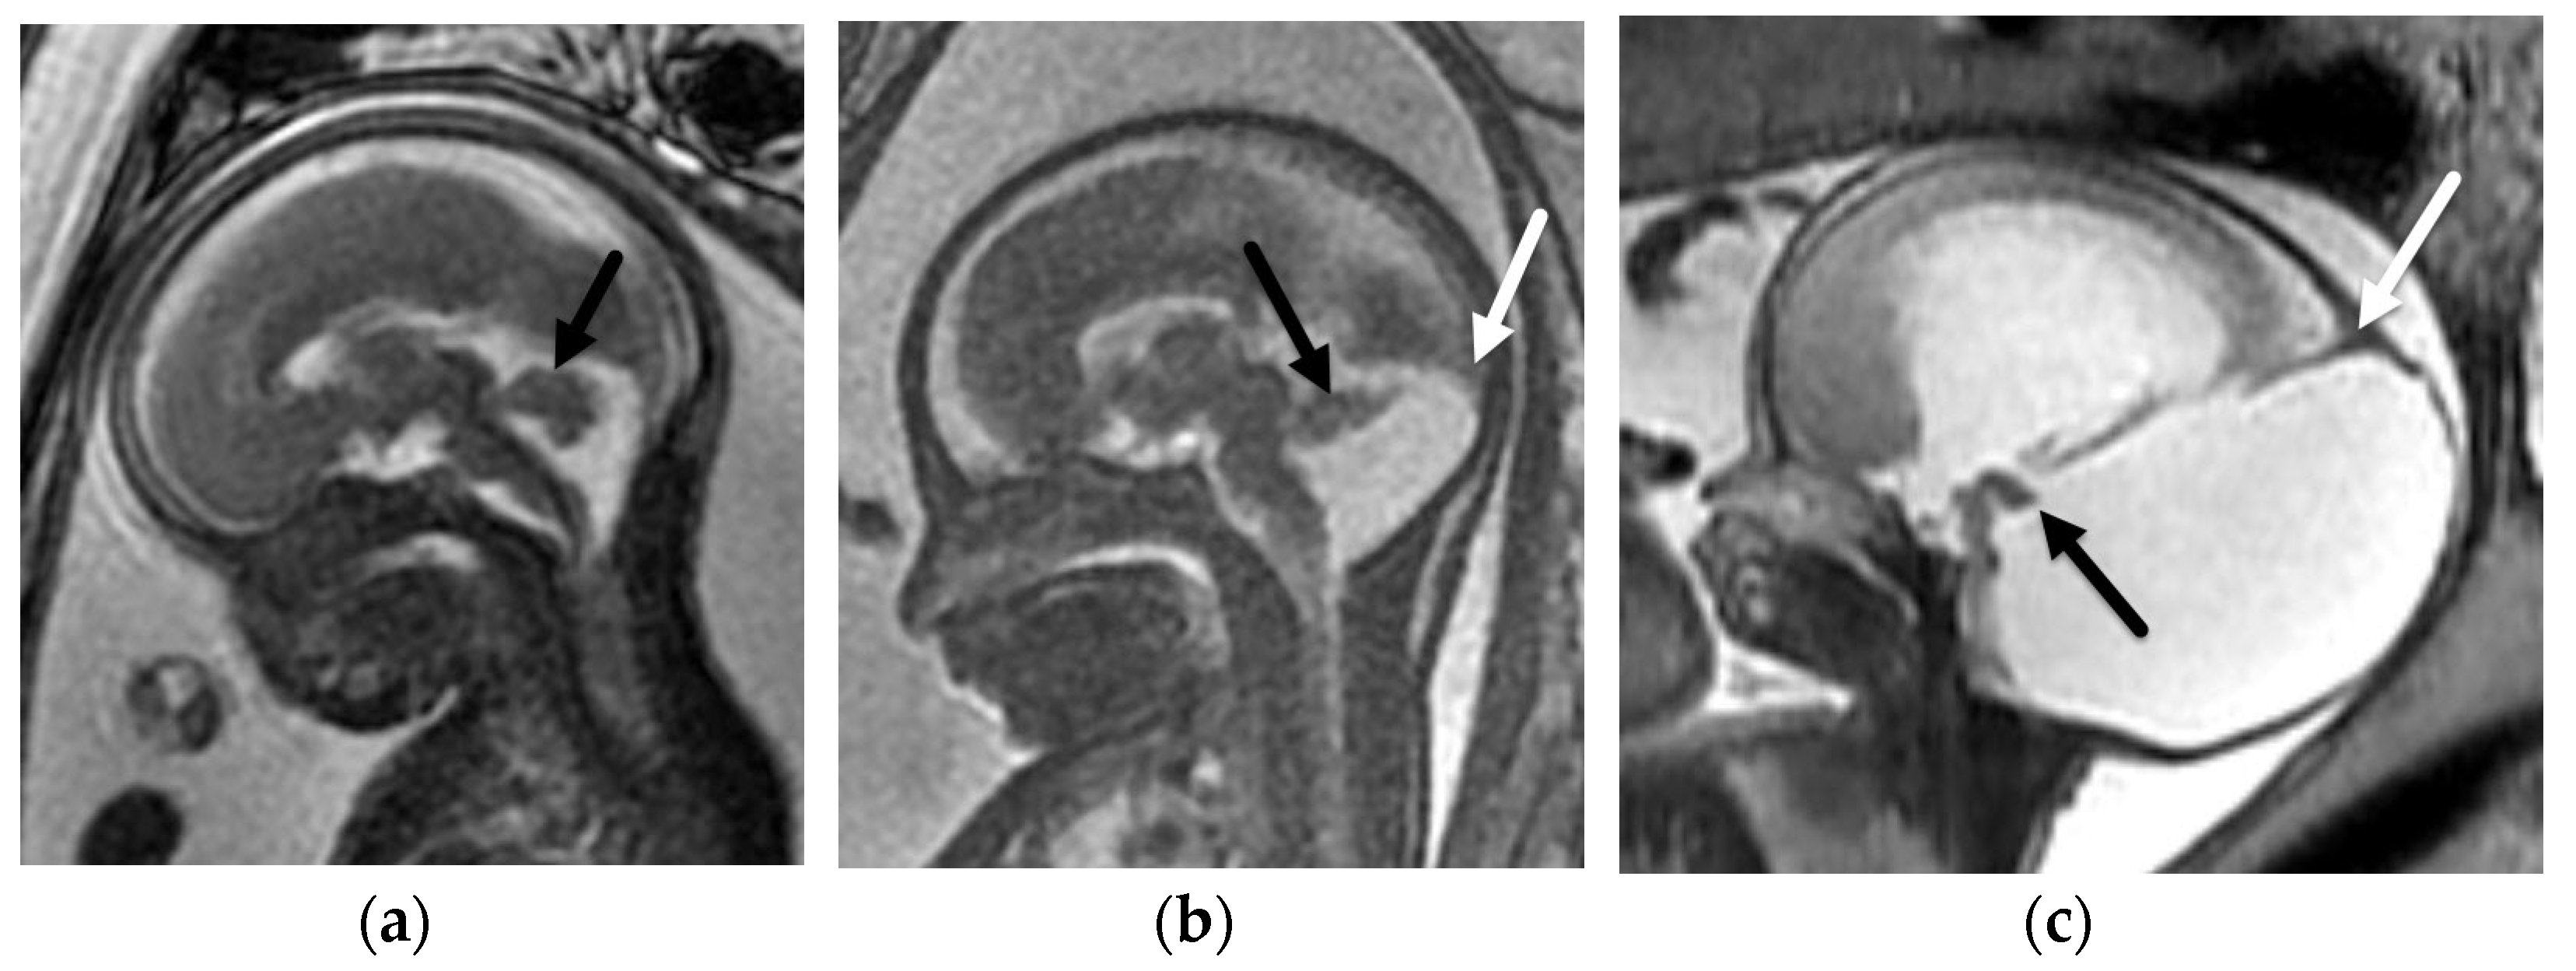

5.1. Dandy-Walker Continuum

- Venkatesan, C.; Kline-Fath, B.; Horn, P.S.; Poisson, K.E.; Hopkin, R.; Nagaraj, U.D. Short- and Long-Term Outcomes of Prenatally Diagnosed Dandy-Walker Malformation, Vermian Hypoplasia, and Blake Pouch Cyst. J. Child Neurol. 2021, 36, 1111–1119. [Google Scholar] [CrossRef]

- Nagaraj, U.D.; Kline-Fath, B.M.; Horn, P.S.; Venkatesan, C. Evaluation of Posterior Fossa Biometric Measurements on Fetal MRI in the Evaluation of Dandy-Walker Continuum. AJNR Am. J. Neuroradiol. 2021, 42, 1716–1721. [Google Scholar] [CrossRef] [PubMed]

- Nagaraj, U.D.; Kline-Fath, B.M.; Calvo-Garcia, M.A.; Vadivelu, S.; Venkatesan, C. Fetal and postnatal MRI findings of Blake pouch remnant causing obstructive hydrocephalus. Radiol. Case Rep. 2020, 15, 2535–2539. [Google Scholar] [CrossRef]